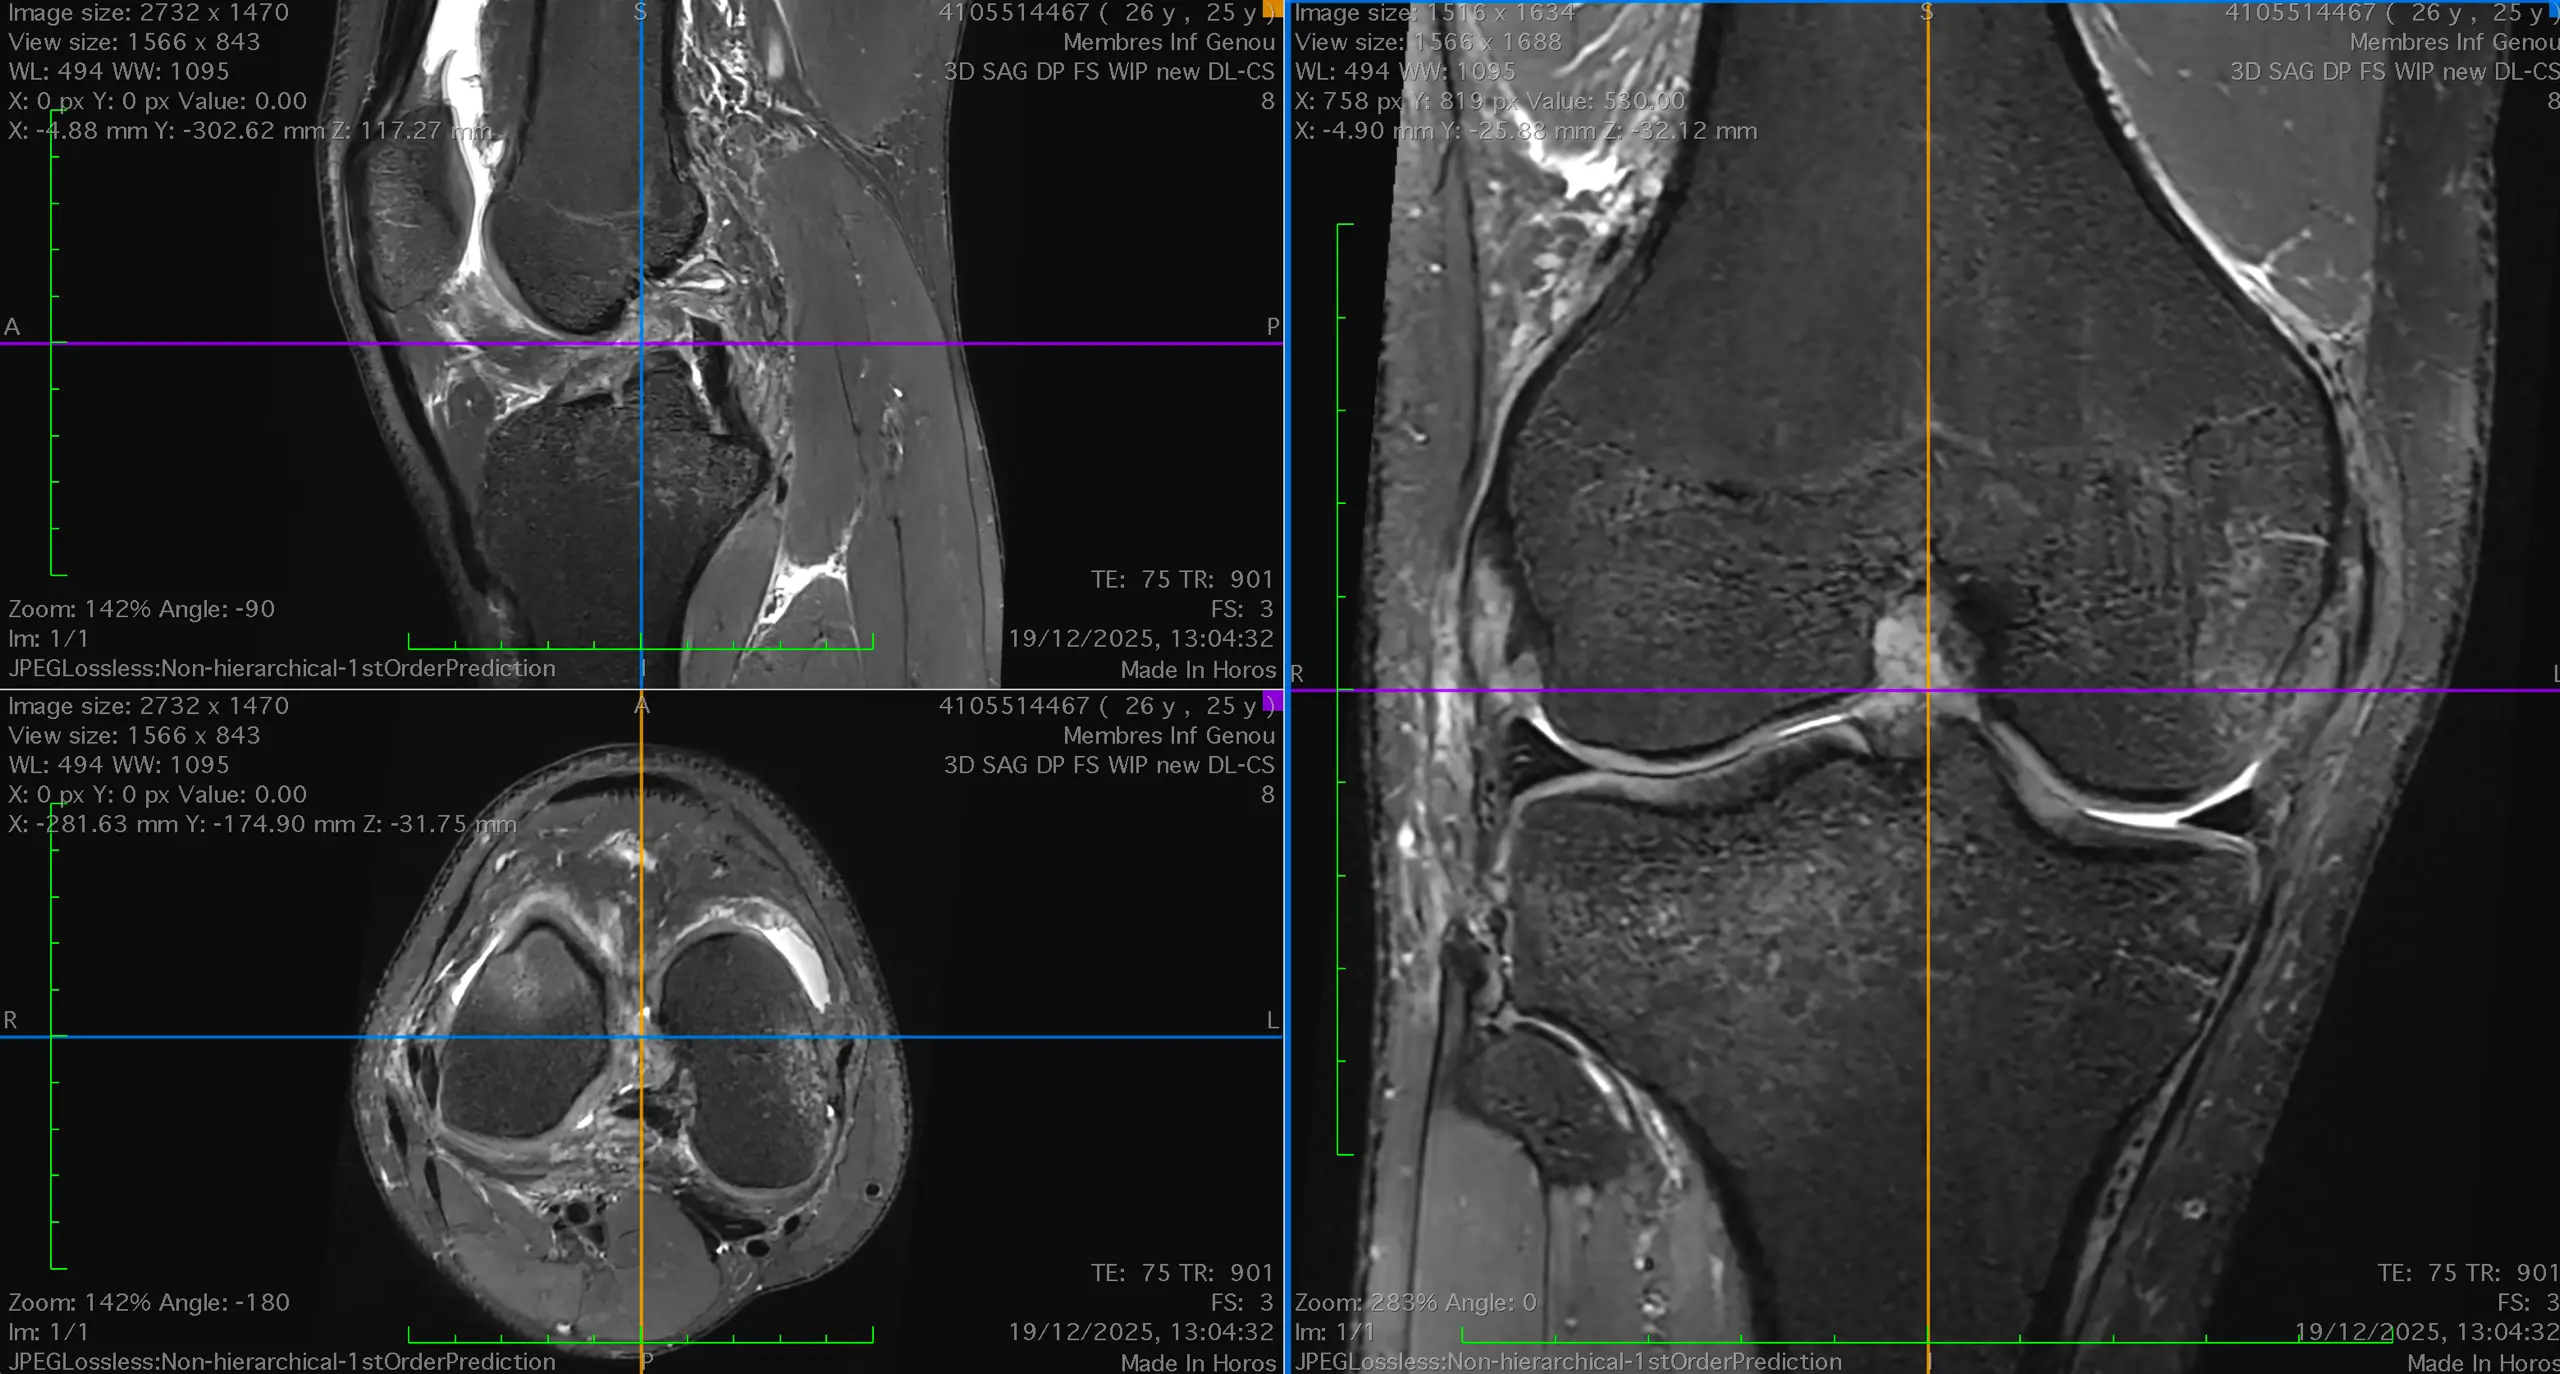

La Chirurgie du Genou

Le Dr Dagher est reconnu particulièrement pour son expertise sur la chirurgie du genou et en particulier la prothèse du genou et la chirurgie du ligament croisé antérieur.

La prise en charge des autres pathologies du genou les plus courantes sont aussi détaillées sur cette page notamment la chirurgie méniscale, la chirurgie de la rotule, la chirurgie de l’arthrose ou encore les différentes technique de réparation du cartilage.